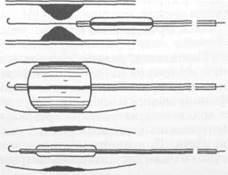

Хирургические методы лечения. Классические реконструктивные оперативные вмешательства можно разделить на четыре группы: I) эндартерэктомия — операция с удалением пораженной интимы; 2) шунтирование; 3) протезирование; 4) эндолюминальная дилатация, дилатация с установкой стента. Больным с сегментарными окклюзиями артерий, не превышающими по протяженности 7—9 см, показана эндартерэктомия. Операция заключается в артериотомии и удалении измененной интимы вместе с атероскле-ротическими бляшками и тромбом. Операцию можно выполнить как закрытым (из поперечного разреза артерии), так и открытым способом (рис. 18.2; 18.3). При закрытом способе имеется опасность повреждения инструментом наружных слоев артериальной стенки. Кроме того, после удаления интимы в просвете сосуда могут остаться ее обрывки, благоприятствующие развитию тромбоза. Вот почему предпочтение следует отдавать открытой эндартерэктомии, при которой производят продольную артериотомию над облитерированным участком артерии и под контролем зрения удаляют измененную интиму с тромбом. Для предупреждения сужения просвет рассеченной артерии может быть расширен путем вшивания заплаты из стенки подкожной вены. При операциях на артериях крупного калибра испольуют заплаты из синтетических тканей (политетрафторэтилен). Некоторые хирурги применяют ультразвуковую эндартерэктомию.

Рис. 18.2. Закрытая эндартерэктомия.